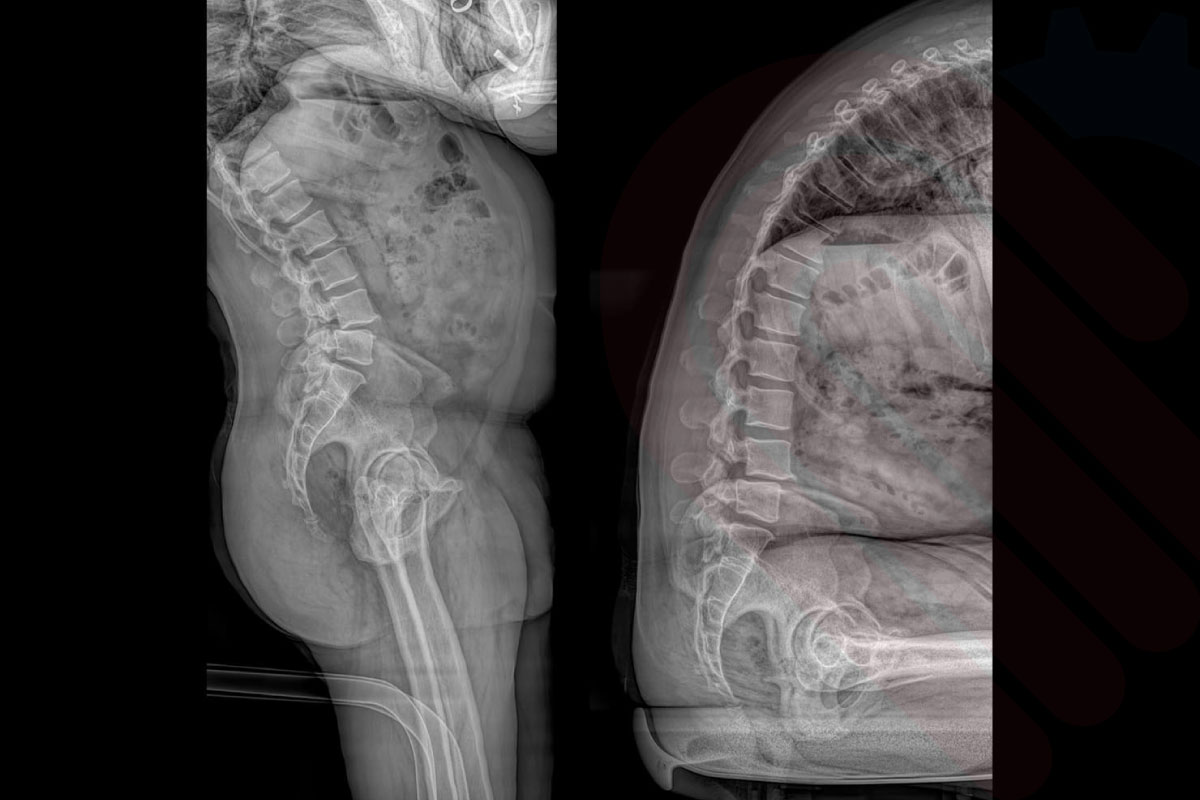

EOSedge, hastaların tarama sırasında doğal ve rahat bir pozisyonda durabilmesi için özel olarak tasarlanmıştır. Dikey ve yatay eksende ayarlanabilir sistem yapısı, hem pediatrik hem yetişkin hastaların en doğru pozisyonda hizalanmasını sağlar. Oturma ve ayakta durma pozisyonları sayesinde skolyoz, diz eklem dejenerasyonu veya kalça displazisi gibi durumlar fizyolojik duruş bozulmadan görüntülenebilir. Ergonomik tasarım, özellikle hareket kısıtlılığı olan hastalarda tarama sürecini kolaylaştırır ve hasta uyumunu artırır*.

Klinik Destek

• Dubousset J, Charpak G, Skalli W, Deguise J, Kalifa G. “Skeletal and spinal imaging with EOS system.” Arch Pediatr. 2008;15(5):665-666.

• → Doğru pozisyonlama, özellikle omurga ve alt ekstremite değerlendirmelerinde ölçüm doğruluğunu artırır ve tekrar çekim ihtiyacını azaltır.